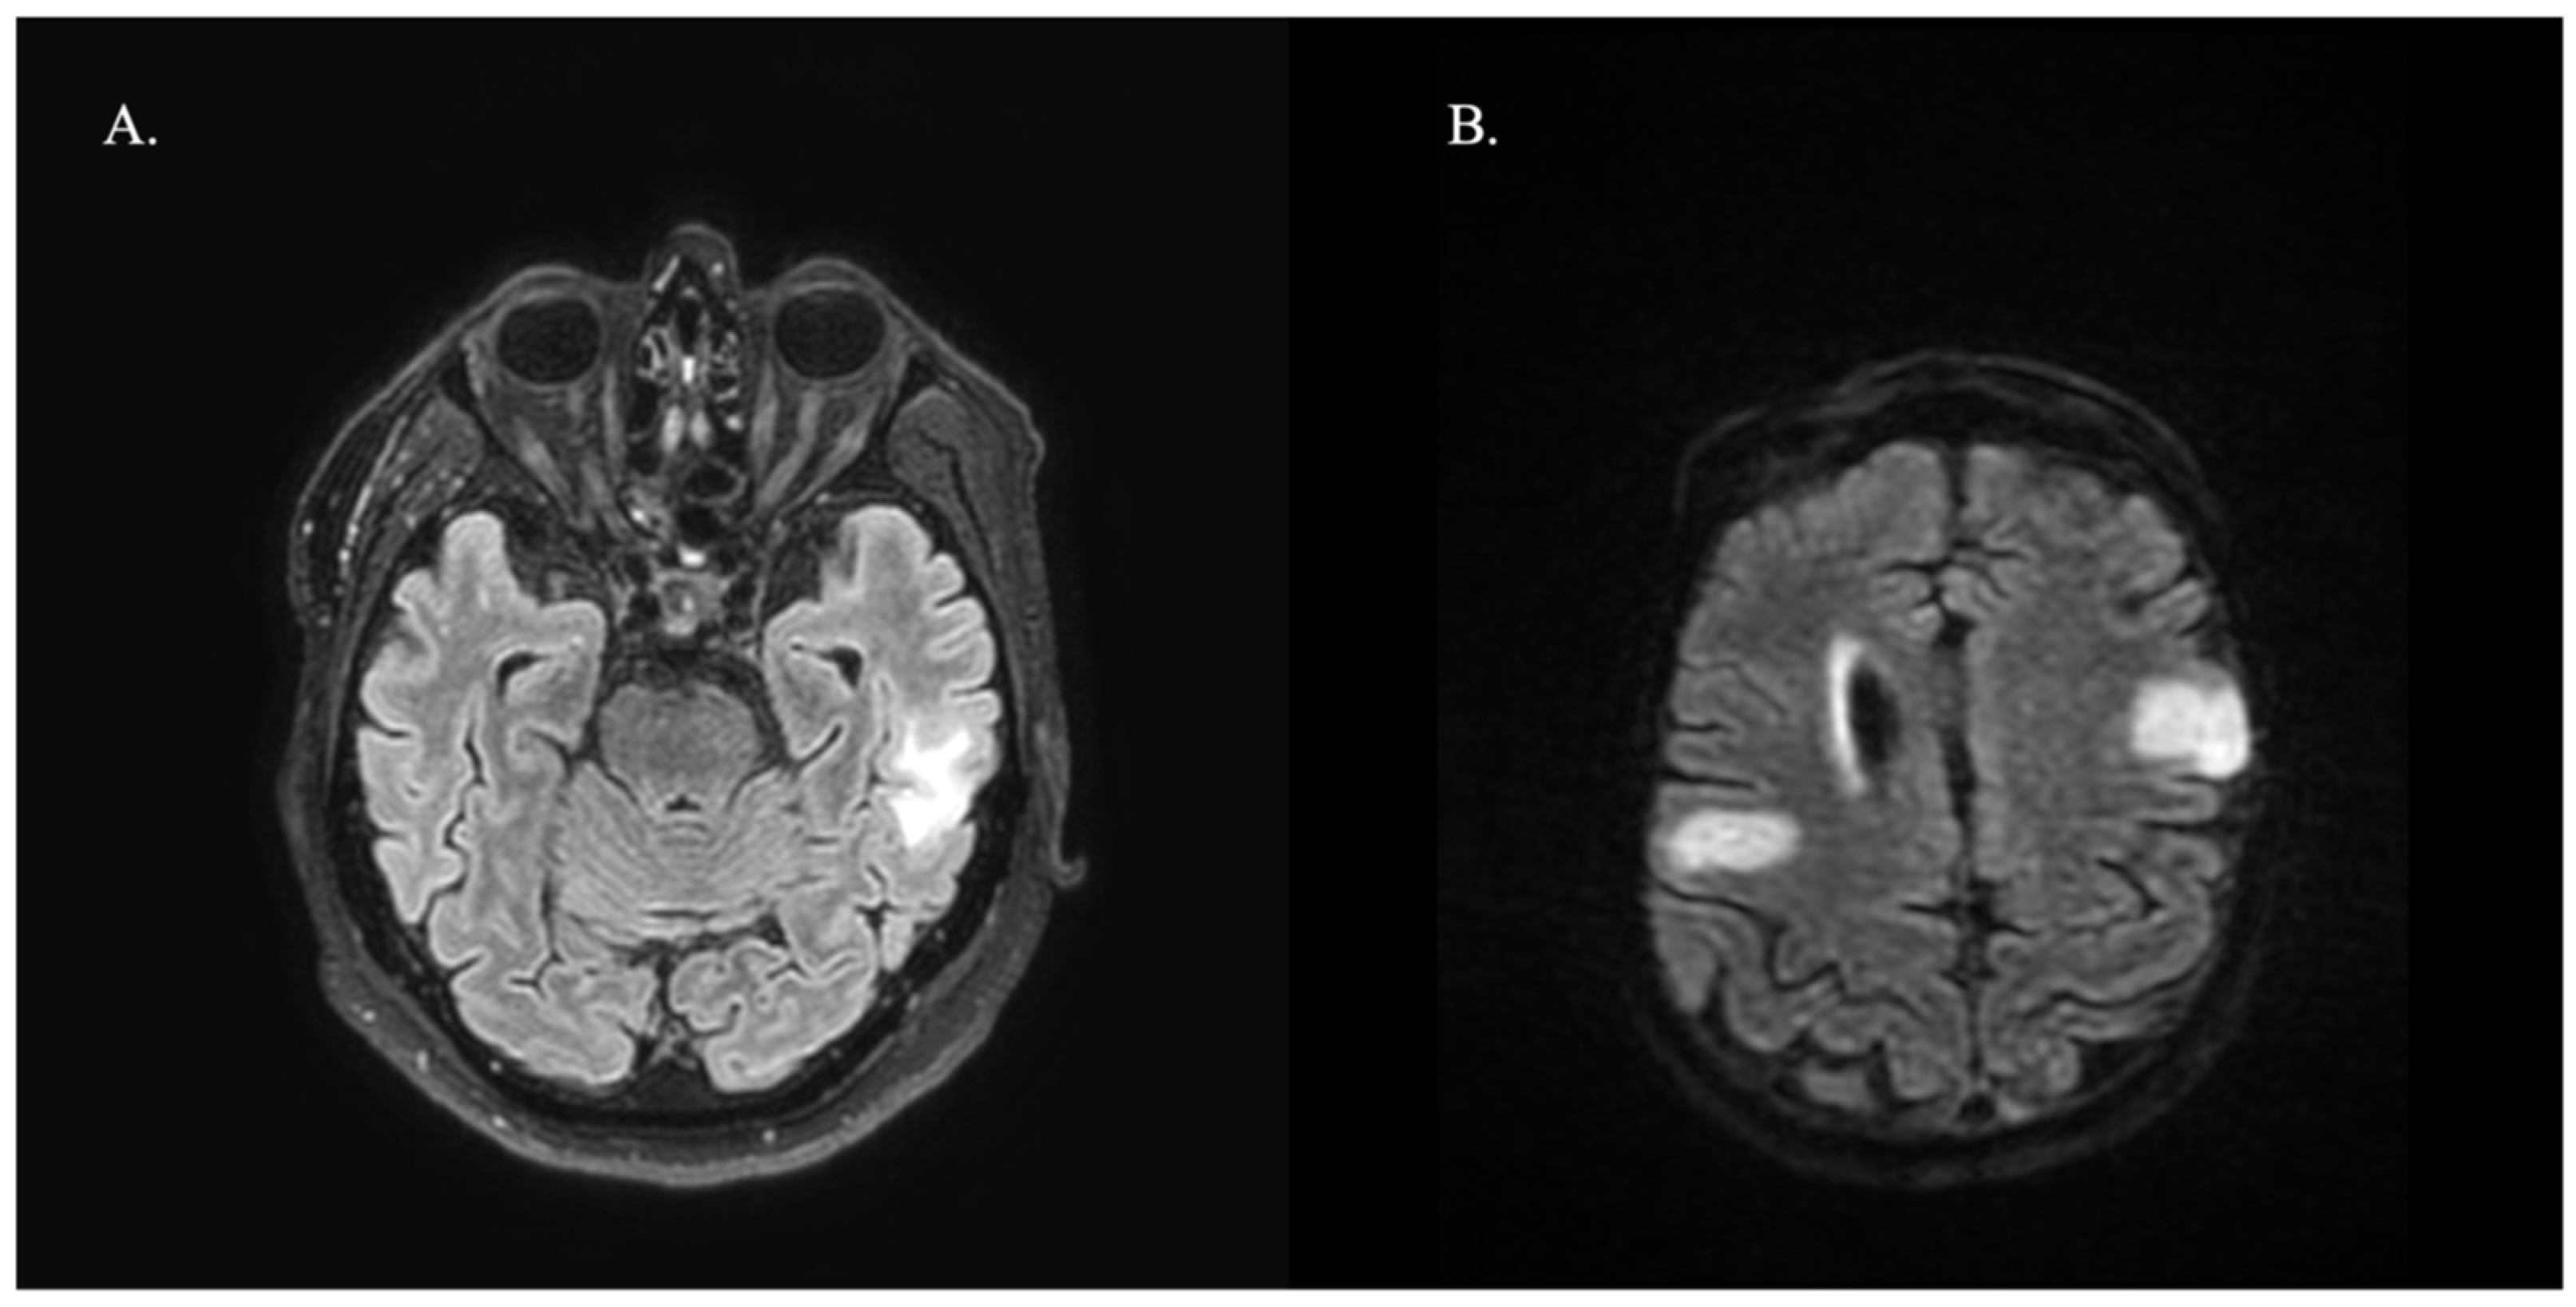

Regarding neuroimaging, all patients had available brain MRI reports, showing T2/FLAIR hyperintensities in 47.4% of cases, most commonly in parietal (35.7%) and frontal (28.6%) locations. Patients diagnosed with LE showed mesial temporal sclerosis in two cases and hyperintense T2 lesions in the hippocampus and amygdala in three cases. Figure 1 shows two examples of brain MRI features. All patients were investigated with full-body CT and three patients with positron emission tomography (PET), which was negative for underlying malignancy. Besides anti-GAD65, patients tested negative for other antibodies in the indirect immunofluorescence panel. CSF pleocytosis was present in seven patients (36.8%) and >2 oligoclonal bands in six (31.6%).

Figure 1. T2-weighted brain MRI with fluid-attenuated inversion recovery (FLAIR) hyperintense lesions attributable to autoimmune encephalitis related to anti-GAD65. (A) A patient with a temporal lesion involving the white matter that clinically presented with limbic encephalitis. (B) Parietal and frontal tumefactive lesions in a patient presenting with epilepsy.